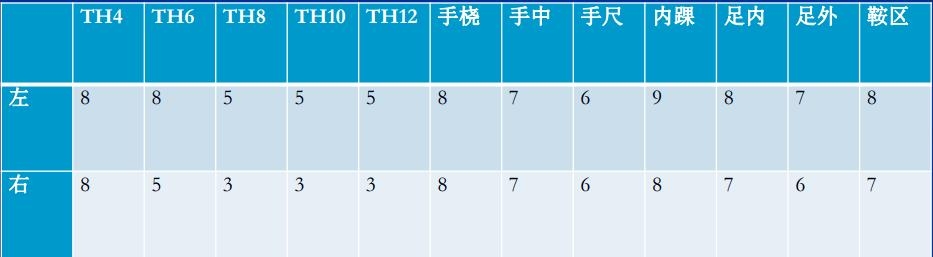

肌容量评估

DXA:计算肌容量

ASM/1.582=5.4kg/m2 <6

双手握力减弱(左侧 5.5kg 右侧 4.7kg 握力计)

行走速度<0.8m/s

诊断为腰椎管狭窄症;邻近节段退变;胸腰段后凸畸形;肌少症。并定制相关治疗措施,最后患者康复出院。